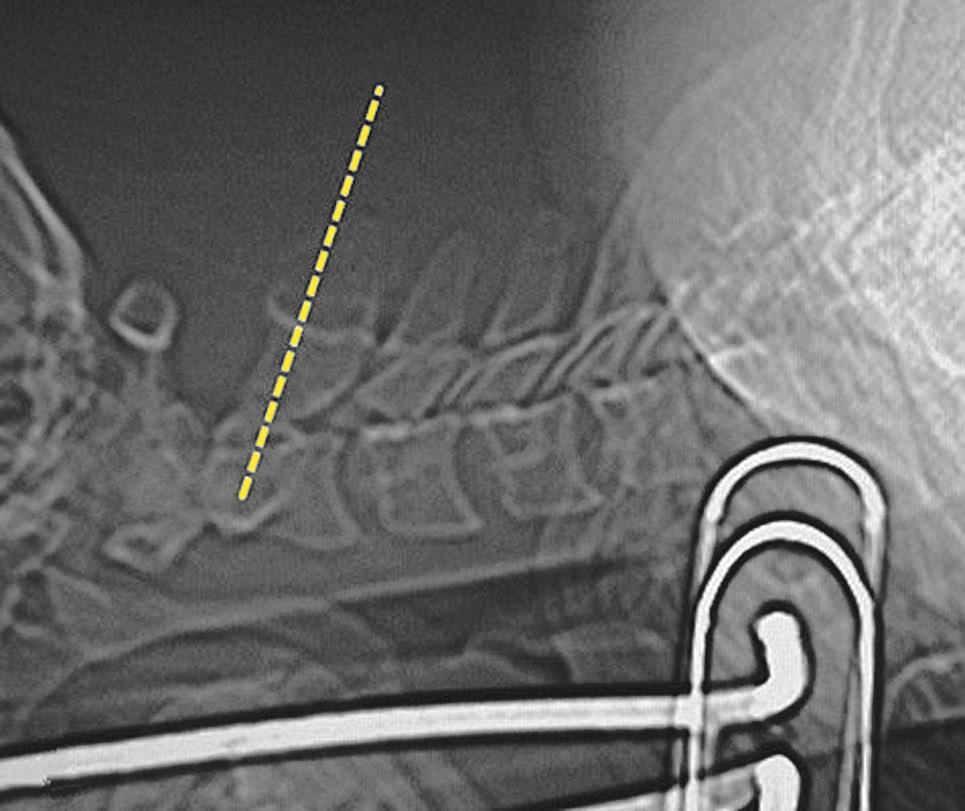

无论什么手术都必须做TOP像扫描,在其上确定手术部位和断层扫描范围。如侧卧位时的椎间隙侧方穿刺入路做脊柱的正位TOP像(图3-3-6),俯卧位时的椎板间入路做脊柱的侧位TOP像(图3-3-7)。

图3-3-6 侧卧位的正位TOP像

A.无髂骨阻挡时机架零度扫描;B.有髂骨阻挡时的角度扫描

一般的CT机架可以调整角度(图3-3-8),调整机架角度进行扫描是寻找操作平面的关键举措,不同的穿刺途径和手术目的要求机架调整的角度也不同,如L 4/5 经椎间隙侧方入路时,如果手术平面无髂骨阻挡,则采用零度扫描(见图3-3-6A、图3-3-8B),否则为了避开髂骨阻挡,机架应向头侧倾斜(图3-3-6B、图3-3-8C);用于射频靶点消融或内镜髓核摘除的椎板间入路,如果扫描角度与椎间隙平行,将多有椎板阻挡(图3-3-9),其要点在于穿刺靶点为直接突出的椎间盘,而穿刺途径又必须避开椎板经过椎板间隙才能成功,因此要求调整到既能显示靶点又经过椎板间隙的角度,一般向足侧倾斜(图3-3-8A、图3-3-10);椎弓根入路则沿椎弓根轴线扫描(图3-3-11)。